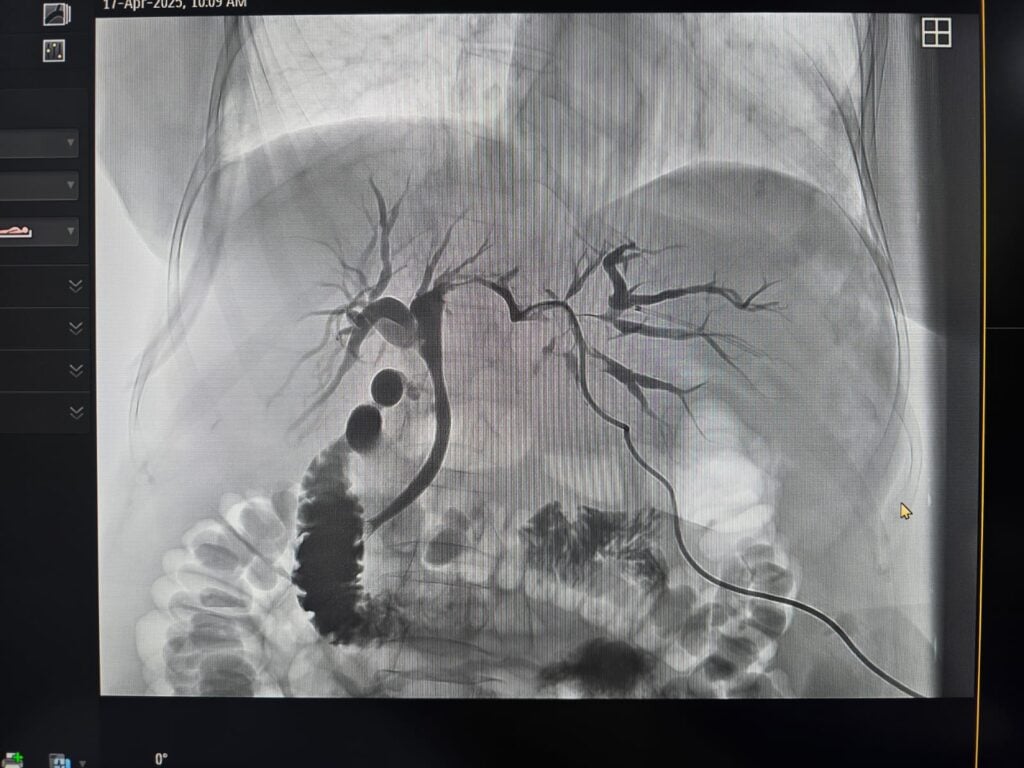

Ambele proceduri au fost efectuate cu ajutorul unor turnuri de laparoscopie de ultimă generație Image 1S Rubina, produse de compania Karl Storz, cunoscută pentru echipamentele sale utilizate în chirurgia minim invazivă.

Aceste sisteme sunt recunoscute pentru capacitatea de imagistică fluorescentă, adică posibilitatea de a evidenția structuri anatomice prin substanțe care emit lumină sub acțiunea unor surse speciale, și pentru acuratețea ridicată a imaginii intraoperatorii.

Potrivit informațiilor transmise, utilizarea acestor tehnologii permite o vizualizare mai clară a structurilor anatomice și poate contribui la creșterea preciziei intervențiilor și la reducerea riscurilor operatorii pentru pacienți.